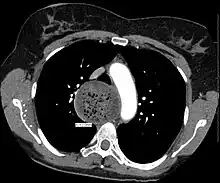

An axial CT image showing marked dilatation of the esophagus in a person with achalasia. -